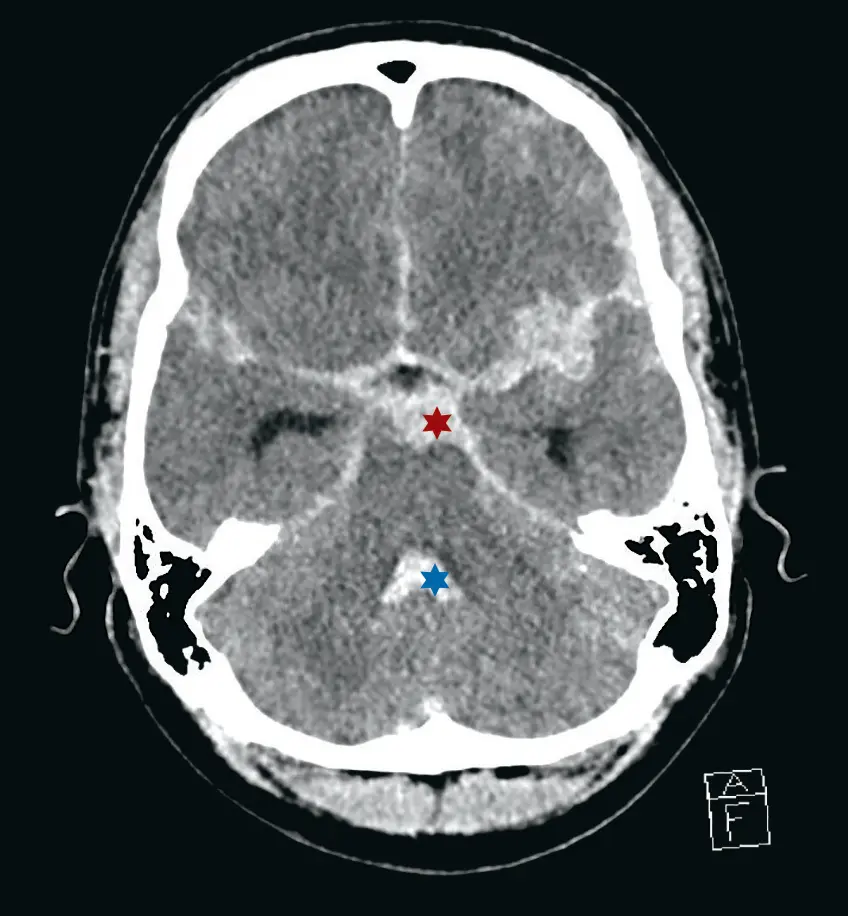

- Einklemmung

- Obere Einklemmung: ipsilaterale Pupillenerweiterung/Anisokorie (N. oculomotorius im Tentoriumschlitz, oberhalb Kleinhirn)

- Untere Einklemmung: Kreislauf- und Ateminsuffizienz (Medulla oblongata im Foramen magnum)

- CCT nativ (Blutung, Ödem, Fraktur, Mittellinienshift)